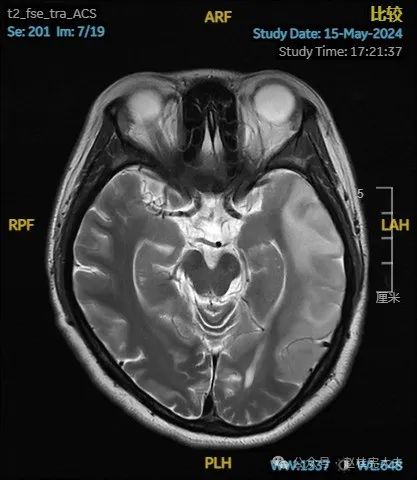

入院后给予精氨酸,左卡尼丁,辅酶Q10,维生素E等治疗。患者病情稳定好转中,2天后意识清楚,语言表达仍欠佳。当天复查颅脑磁共振如下:

以上为患者发病后3次的颅脑磁共振片子,临床诊断基本上可以确认了,希望患者逐渐恢复!